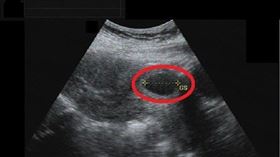

孕婦子宮「空空」 醫驚:胎兒在腹腔

每一個新生命的孕育都是美妙的,但對準媽媽來說每個孕程...

雙胞胎供血不均 腹中胎兒治療救命

一名31歲的許小姐在妊娠20週多時發現腹中胎兒臍帶血...